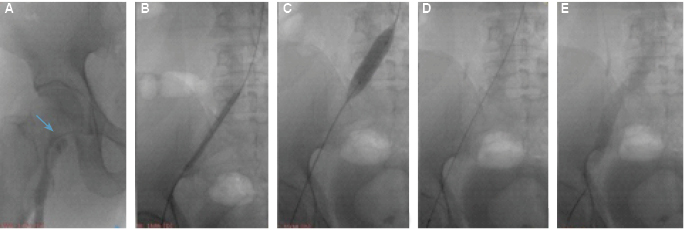

Figura 2: A. Flebografía en donde se muestra amputación de medio de contraste en vena femoral común e iliacas. B y C. Angioplastia venosa. D. Liberación de stent (Zilver Vena Cook Medical). E. Flebografía realizada después de la colocación del stent; típicamente, demuestra flujo rápido a través de la lesión tratada.

El procedimiento deberá ser realizado bajo anestesia general, ya que a diferencia de las angioplastias arteriales, la dilatación venosa suele ser dolorosa y poco tolerada por el sujeto, incluso con sedación. El abordaje puede ser a través de la vena yugular, femoral ipsilateral o contralateral, siempre y cuando se encuentre libre de enfermedad, o vena poplítea ipsilateral con la persona en posición prona; siempre con la utilización del ultrasonido Doppler para la punción (Figura 2). Además, el enfermo debe recibir anticoagulación a 18/UI/kg. Dependiendo del sitio anatómico obstruido y de la extensión del trombo, se planea la reconstrucción. En los casos donde el paciente tiene compromiso del filtro de vena cava, se prefiere realizar la reconstrucción por arriba del sector renal; en este procedimiento, se utiliza la técnica conocida como “crushing”, la cual consiste en aplastar o atrapar el filtro de vena cava contra la pared de la misma mediante la colocación de un stent desnudo, balón expandible, de alta fuerza radial, como un stent Palmaz (Cordis, Miami Lakes, Fla).11 Cuando existe ligadura quirúrgica previa por trauma, atresia o trombosis de larga evolución, la vena cava inferior (VCI) puede ser notablemente más estrecha o no existir un segmento de su longitud. Para el abordaje de estas lesiones, se utilizan técnicas convencionales endovasculares como la manipulación de las guías para la recanalización de obstrucciones severas o conectar segmentos discontinuos de la cava.12 Si la recanalización aguda es necesaria, pueden realizarse accesos bidireccionales, llevando a cabo la captura de una de las guías para obtener un sitio de entrada y poder hacer la angioplastia con balón y la colocación de un stent que una el segmento discontinuo u obstruido.